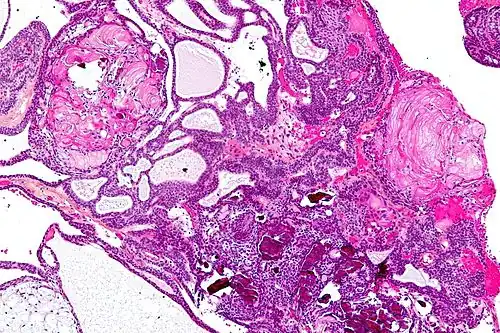

On macroscopic examination, craniopharyngiomas are cystic or partially cystic with solid areas. On light microscopy, the cysts are seen to be lined by stratified squamous epithelium. Keratin pearls may also be seen. The cysts are usually filled with a yellow, viscous fluid rich in cholesterol crystals. Of a long list of possible symptoms, the most common presentations include headaches, growth failure, and bitemporal hemianopsia.

Micrograph showing the characteristic features of an adamantinomatous craniopharyngioma - cystic spaces, calcifications, and "wet" keratin, HPS stain -

Micrograph showing a papillary craniopharyngioma, HPS stain